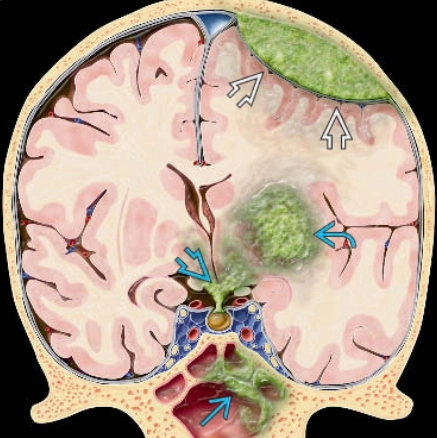

Di căn nhu mô não (Parenchymal metastases)